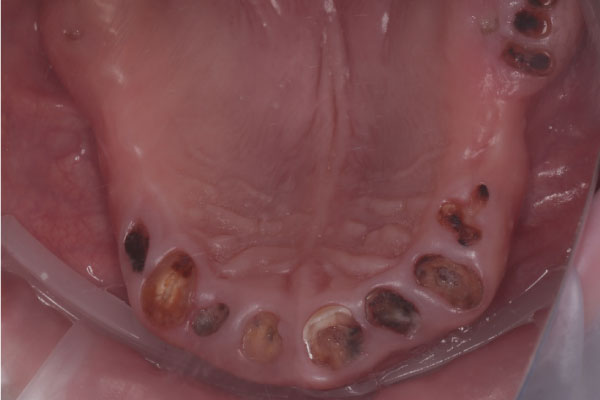

Имплантация зубов: фото «До» и «После»

Фото ДО

All-on-4